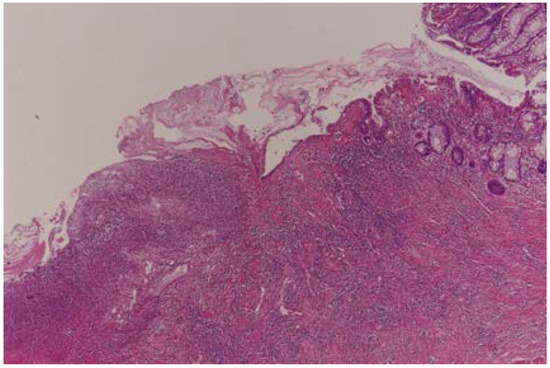

- Dworak, O.; Keilholz, L.; Hoffmann, A. Pathological features of rectal cancer after preoperative radiochemotherapy. Int. J. Color. Dis. 1997, 12, 19–23. [Google Scholar] [CrossRef] [PubMed]

- Ryan, R.; Gibbons, D.; Hyland, J.M.; Treanor, D.; White, A.; Mulcahy, H.E.; O’Donoghue, D.P.; Moriarty, M.; Fennelly, D.; Sheahan, K. Pathological response following long-course neoadjuvant chemoradiotherapy for locally advanced rectal cancer. Histopathology 2005, 47, 141–146. [Google Scholar] [CrossRef]

- Chen, H.Y.; Feng, L.L.; Li, M.; Ju, H.Q.; Ding, Y.; Lan, M.; Song, S.M.; Han, W.D.; Yu, L.; Wei, M.B.; et al. College of American Pathologists Tumor Regression Grading System for Long-Term Outcome in Patients with Locally Advanced Rectal Cancer. Oncologist 2021, 26, e780–e793. [Google Scholar] [CrossRef] [PubMed]